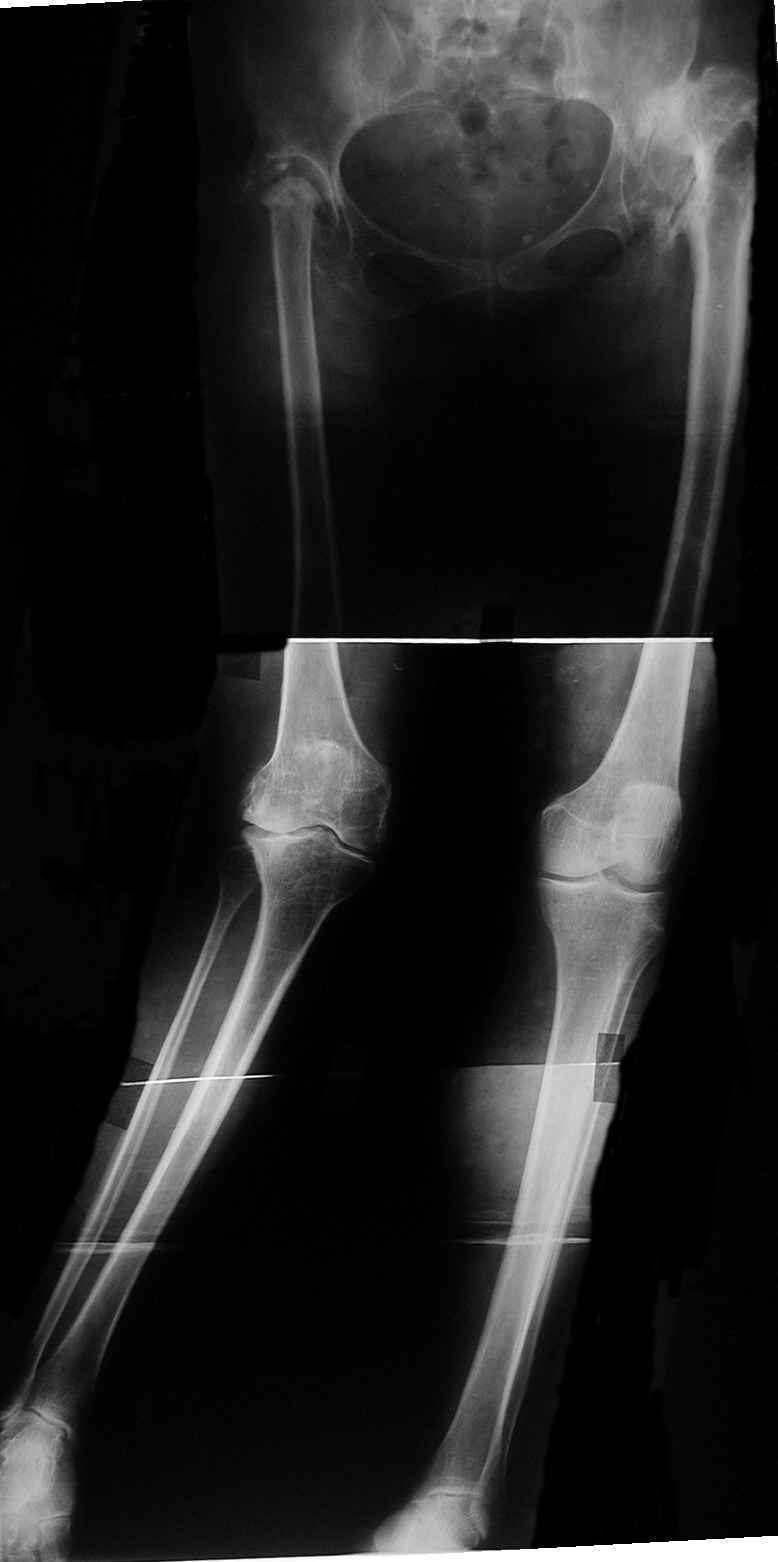

В настоящий момент пациентка поступила с жалобами на боль, деформацию правого коленного сустава. При осмотре вальгусная деформация на уровне правого коленного сустава 20 град., в нагрузке увеличивается до 30. Движения в правом коленном суставе болезненные, амплитуда 80/180 град. Опороспособность правой нижней конечности нарушена засчёт тотальной нестабильности правого коленного сустава. Стойкой контрактуры в неоартрозе на уровне правого тазобедренного сустава нет. В левом т/б суставе движения качательные, имеется сгибательно-приводящая контрактура, но сохранена опороспособность конечности.

1-м этапом планируем выполнить эндопротезирование правого тазобедренного сустава с использованием ножки типа Wagner. 2-м этапом – эндопротезирование правого коленного сустава. После восстановления функции суставов и опороспособности правой нижней конечности планируем выполнить эндопротезирование левого тазобедренного сустава.

Для т\б сустава, судя по снимку, не обязательно использовать Вагнер, можно любой с дистальной фиксацией (Цваймюллер или ЭС-тайпер)